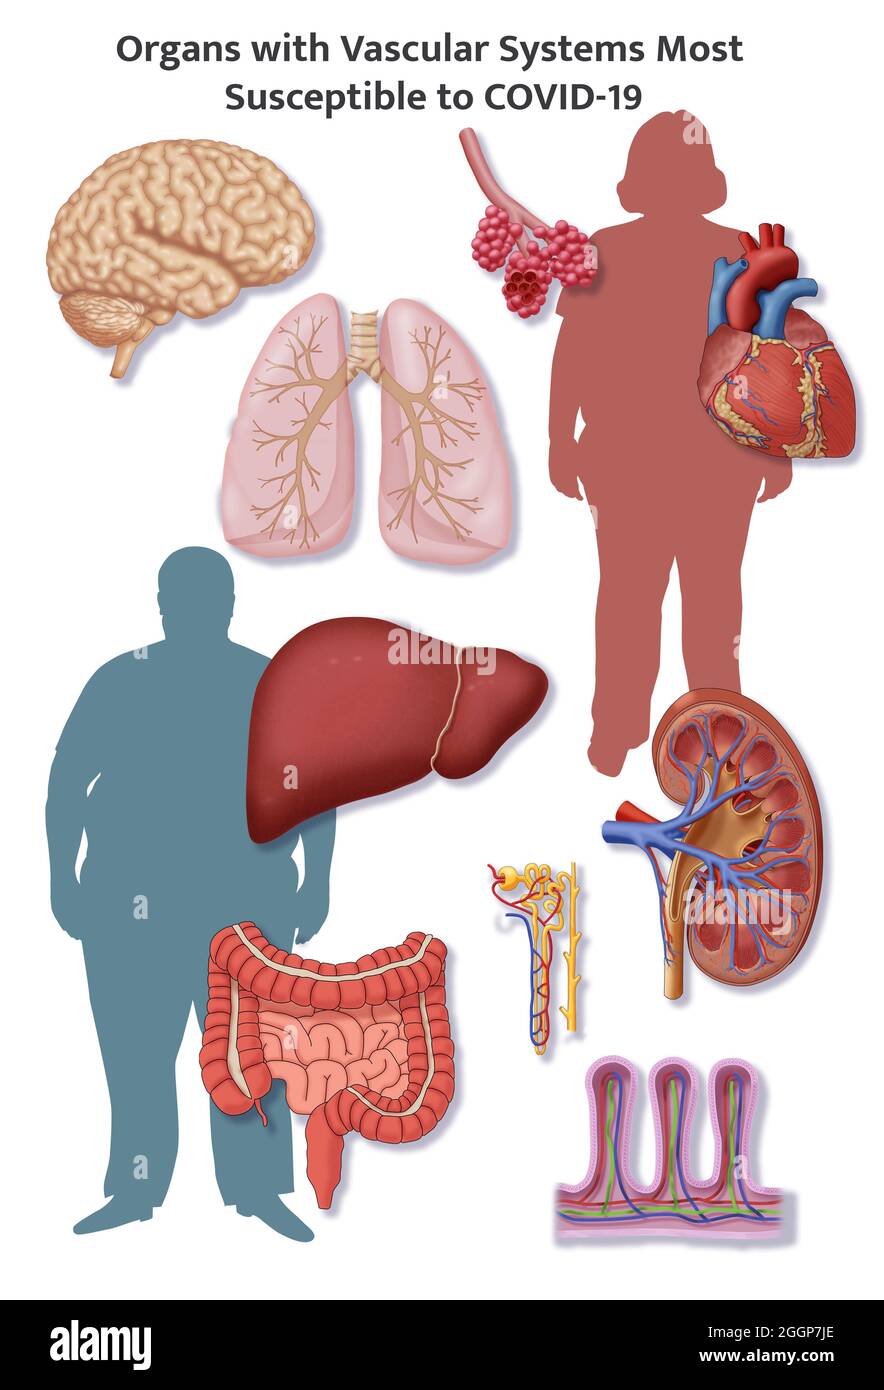

A selection of organs that have delicate vascular systems. Stock Photohttps://www.alamy.com/image-license-details/?v=1https://www.alamy.com/a-selection-of-organs-that-have-delicate-vascular-systems-image440582659.html

A selection of organs that have delicate vascular systems. Stock Photohttps://www.alamy.com/image-license-details/?v=1https://www.alamy.com/a-selection-of-organs-that-have-delicate-vascular-systems-image440582659.htmlRM2GGP7JY–A selection of organs that have delicate vascular systems.

A selection of organs that have delicate vascular systems. Stock Photohttps://www.alamy.com/image-license-details/?v=1https://www.alamy.com/a-selection-of-organs-that-have-delicate-vascular-systems-image440582646.html

A selection of organs that have delicate vascular systems. Stock Photohttps://www.alamy.com/image-license-details/?v=1https://www.alamy.com/a-selection-of-organs-that-have-delicate-vascular-systems-image440582646.htmlRM2GGP7JE–A selection of organs that have delicate vascular systems.

A selection of organs that have delicate vascular systems. Stock Photohttps://www.alamy.com/image-license-details/?v=1https://www.alamy.com/a-selection-of-organs-that-have-delicate-vascular-systems-image440582624.html

A selection of organs that have delicate vascular systems. Stock Photohttps://www.alamy.com/image-license-details/?v=1https://www.alamy.com/a-selection-of-organs-that-have-delicate-vascular-systems-image440582624.htmlRM2GGP7HM–A selection of organs that have delicate vascular systems.

A selection of organs that have delicate vascular systems. Stock Photohttps://www.alamy.com/image-license-details/?v=1https://www.alamy.com/a-selection-of-organs-that-have-delicate-vascular-systems-image440582657.html

A selection of organs that have delicate vascular systems. Stock Photohttps://www.alamy.com/image-license-details/?v=1https://www.alamy.com/a-selection-of-organs-that-have-delicate-vascular-systems-image440582657.htmlRM2GGP7JW–A selection of organs that have delicate vascular systems.